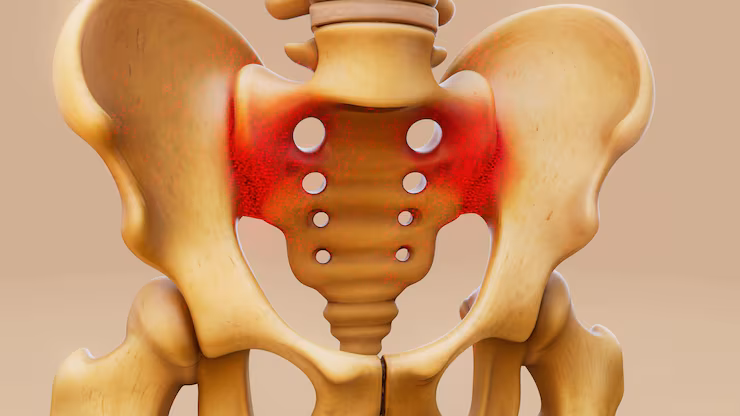

Pelvi acetabular surgeries are specialized orthopedic procedures performed to treat complex fractures and injuries involving the pelvis and acetabulum (hip socket). These injuries commonly occur due to high-impact trauma such as road traffic accidents, falls from height, or industrial injuries and require precise surgical intervention to restore pelvic stability and hip joint function.

Management of pelvic and acetabular fractures demands detailed preoperative planning using advanced imaging such as CT scans and three-dimensional reconstruction. Surgical fixation is performed using specialized plates and screws to accurately realign fractured bones, preserve joint congruity, and minimize long-term complications.